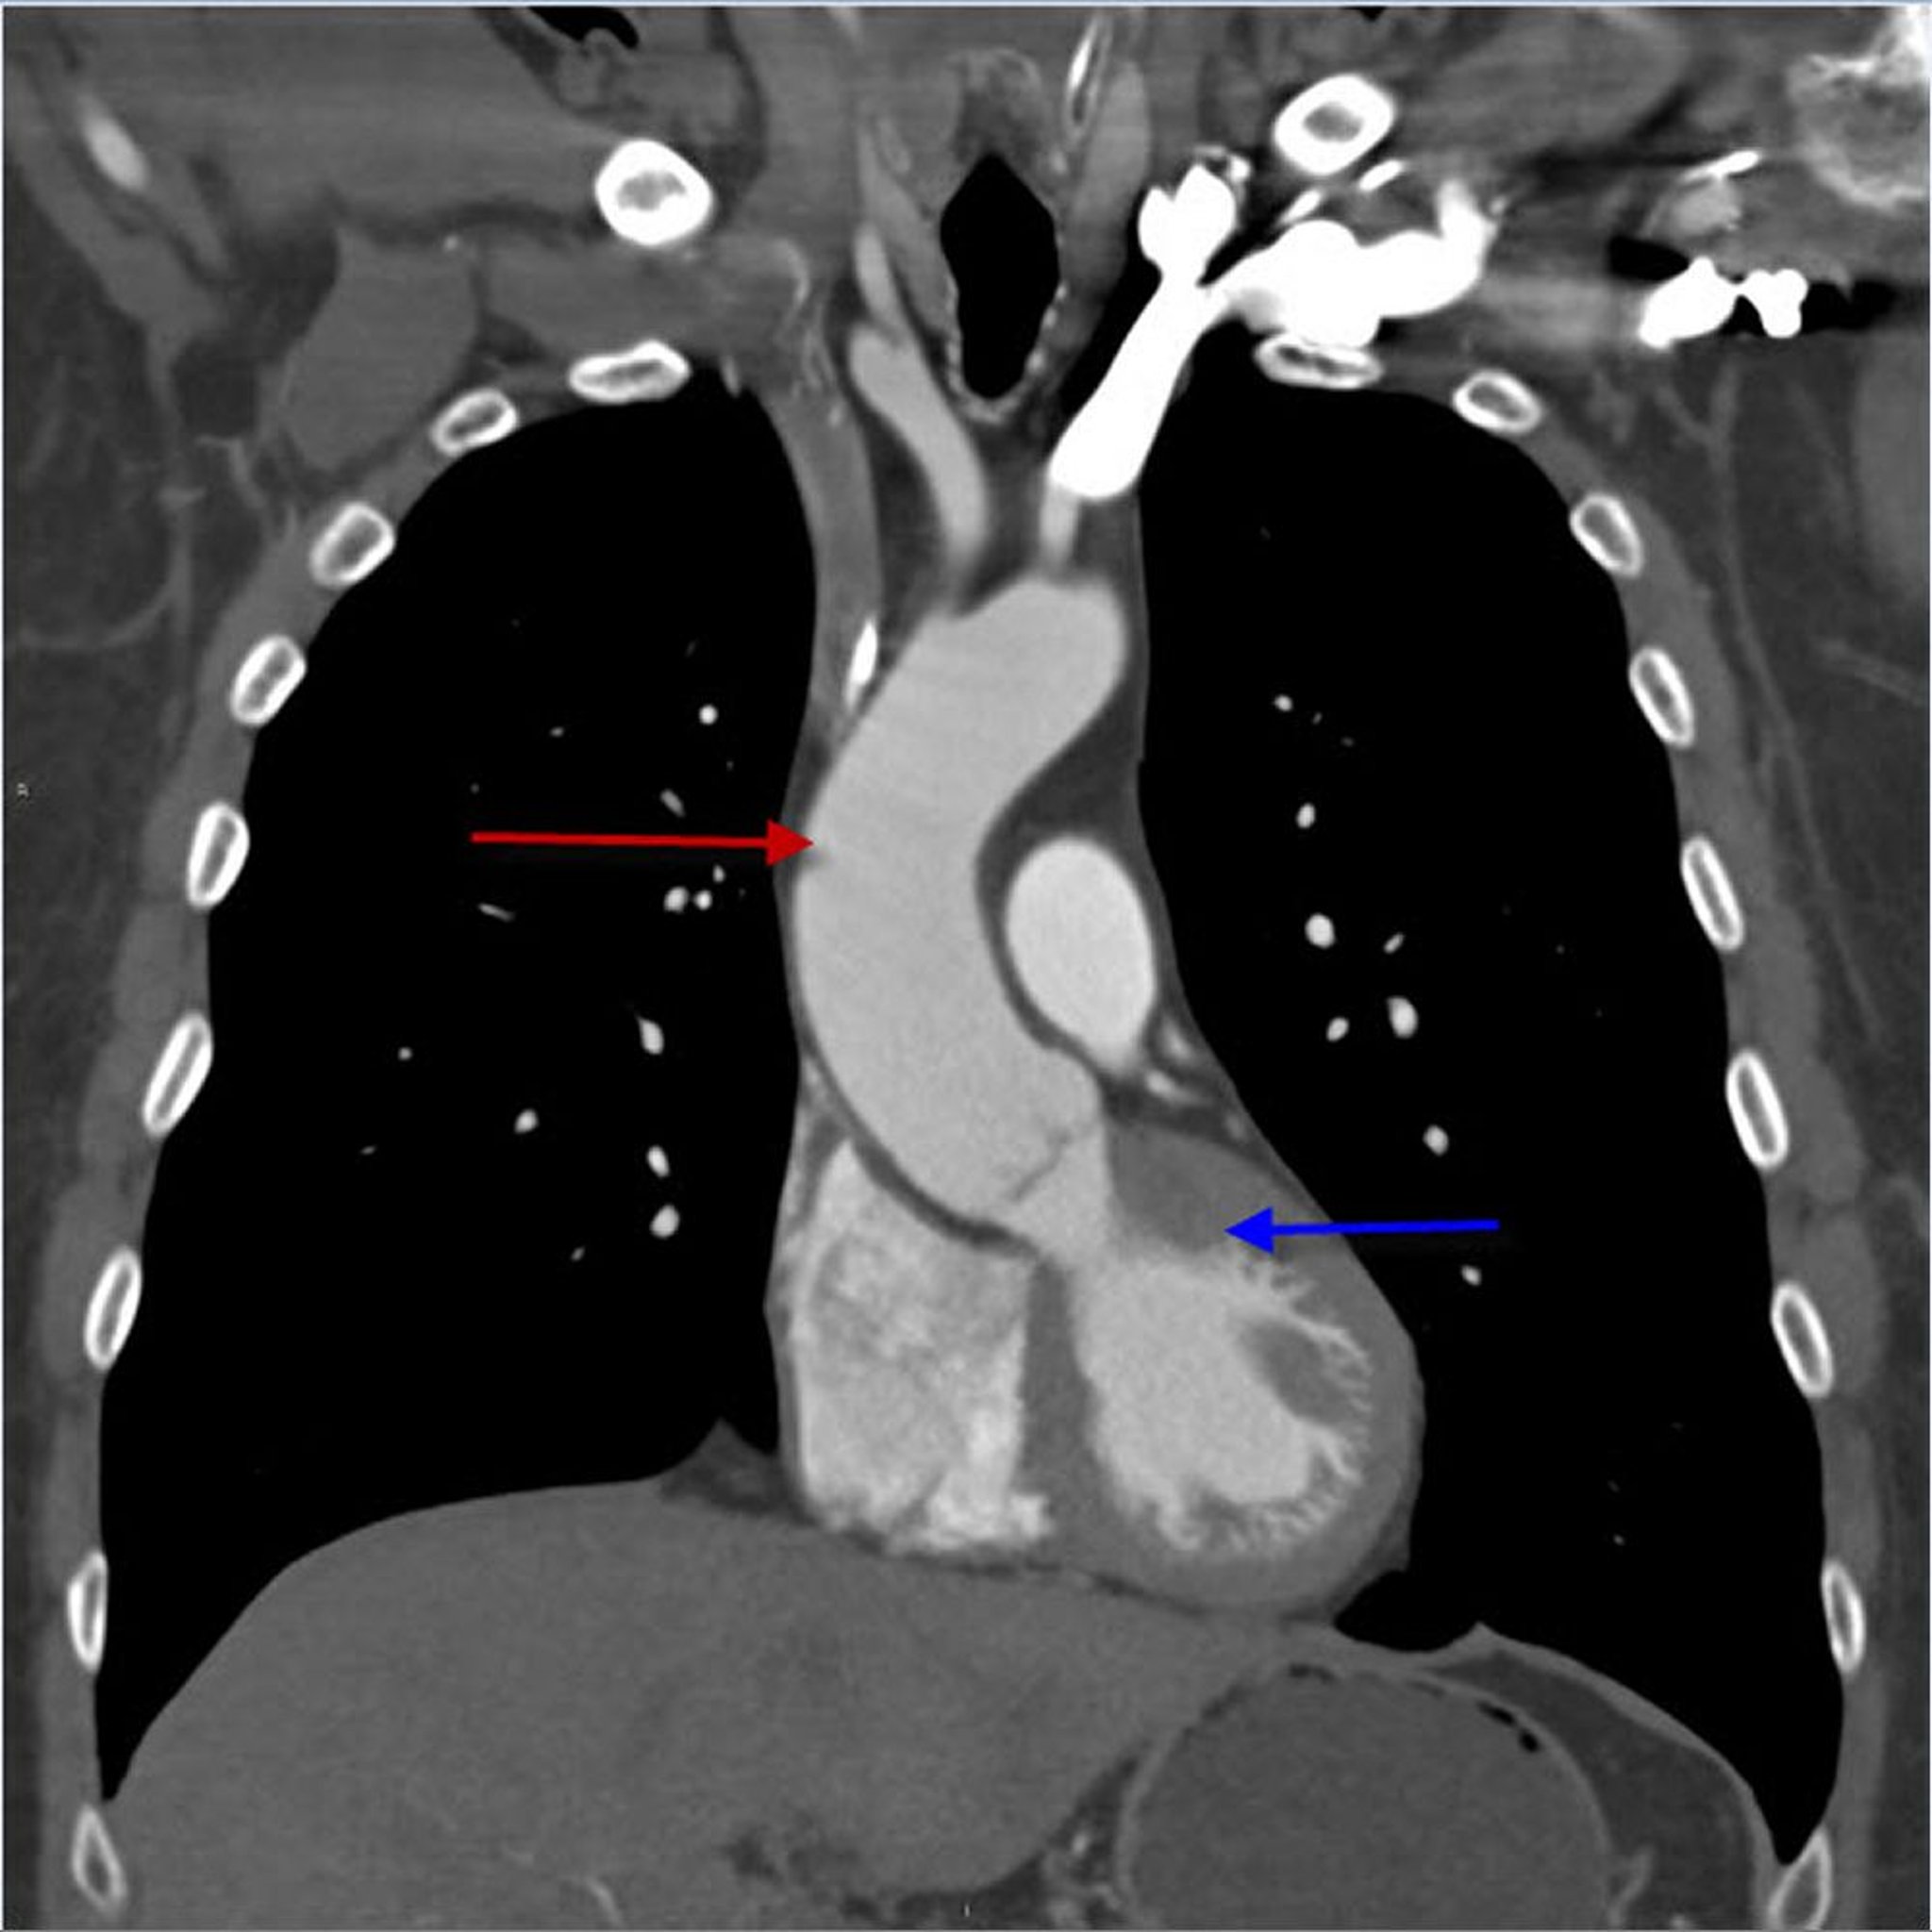

CTA (khung nhìn đứng ngang) của lồng ngực cho thấy động mạch chủ ngực lên

Hình ảnh này cho thấy động mạch chủ ngực lên (mũi tên màu đỏ) phát sinh từ tâm thất trái (mũi tên màu xanh lam).